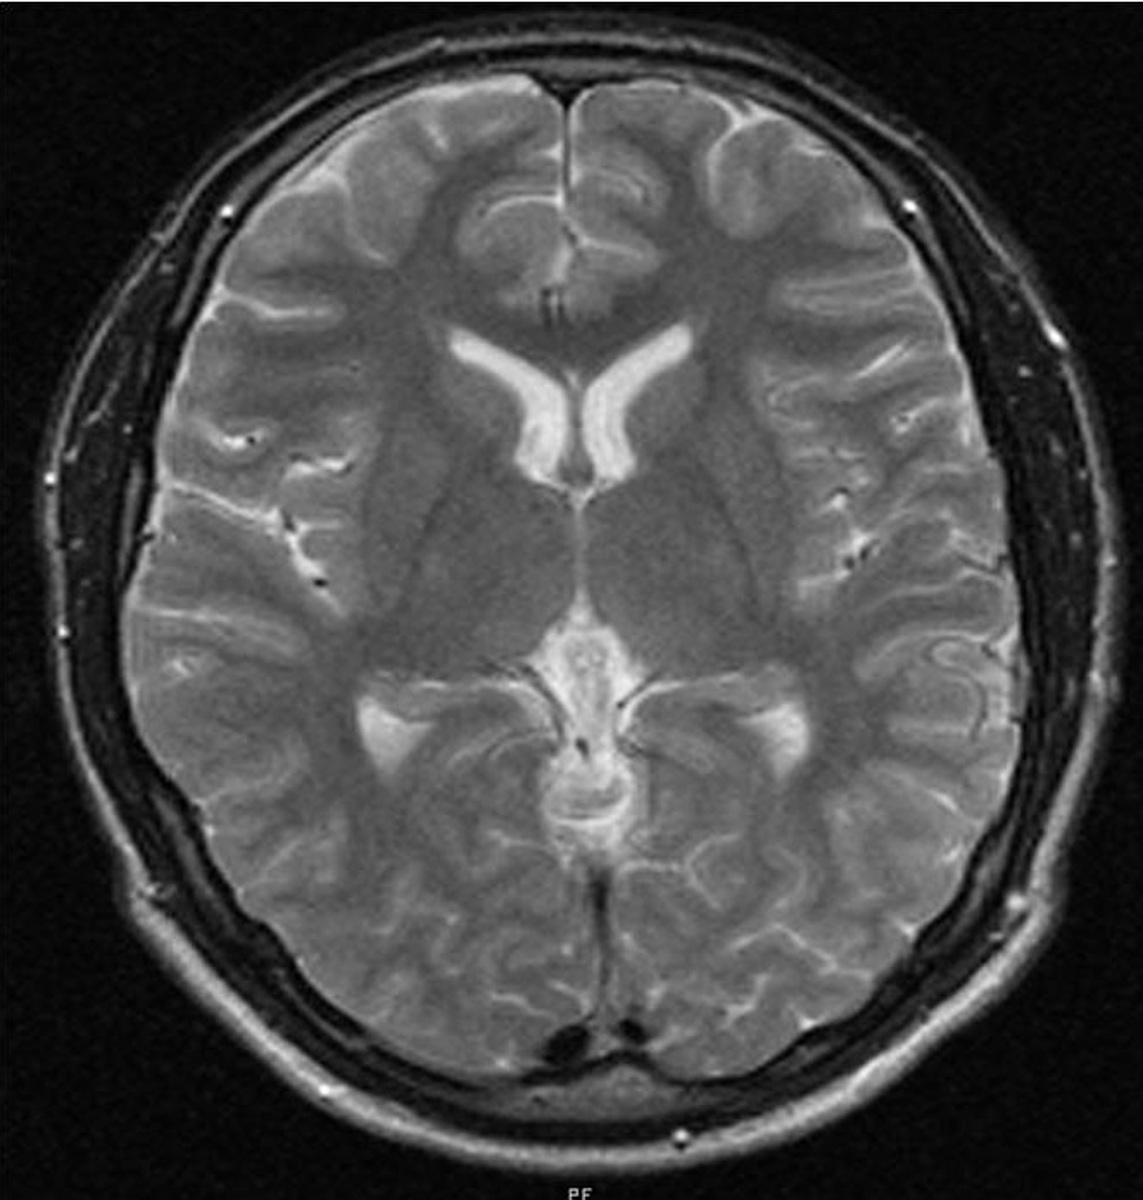

- Магнитно-резонансная томография (МРТ) головного или спинного мозга с контрастным усилением: Это «золотой стандарт» в диагностике менингиом. МРТ позволяет получить детальные изображения структур мозга и выявить опухоль, определить ее точное расположение, размер, отношение к окружающим тканям и степень накопления контрастного вещества. Менингиома часто имеет характерный вид на МРТ с равномерным интенсивным накоплением контраста.